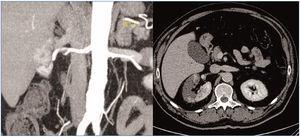

Ante el intenso dolor y la elevación de LDH, se decide solicitar una tomografía computarizada que evidencia un extenso infarto renal derecho con un defecto de repleción en la arteria renal principal, justo proximal a su trifurcación (figura 1).

Figura 1. Diferentes proyecciones del infarto renal derecho en la tomografía computarizada